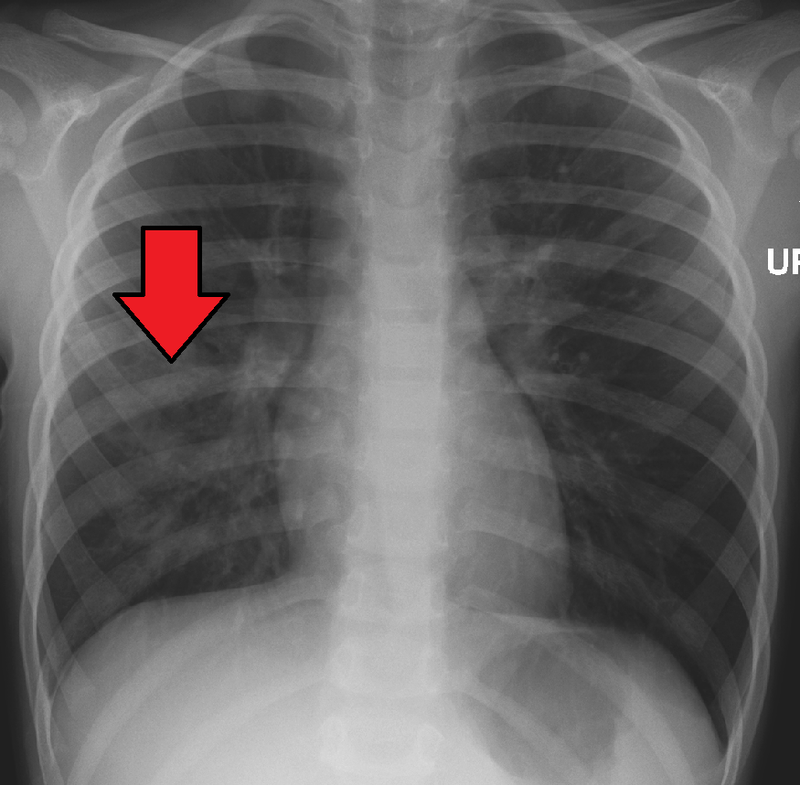

Three common patterns of pneumonia may be detected on chest X-ray which include:

- Lobar pneumonia

Lobar Pneumonia

Lobar pneumonia is characterized by the consolidation of a whole lung lobe.

Lobar pneumonia is typically caused by bacteria which include:

- Streptococcus pneumonia (95 percent)

- Klebsiella pneumonia

Typical gross lobar pneumonia presents in phases:

- Congestion resulting from edema and clogged vessels

- Exudate, neutrophils, and hemorrhage cause red hepatization, which gives the typically spongy lung a solid consistency by filling the alveolar air spaces

- Gray hepatization as a result of red blood cell (RBC) breakdown in the exudate